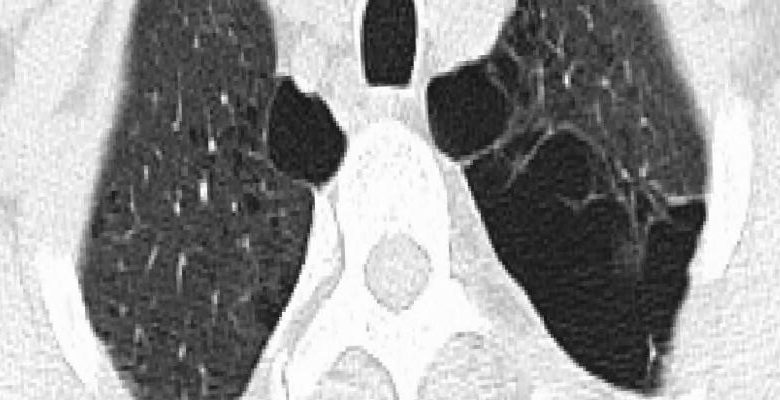

Yaşlanmayla ve çeşitli sebeplerle bronşların elastikiyeti azalır, ödem oluşur ve daralma başlar. Bu duruma kronik tıkayıcı akciğer hastalıkları (KOAH) adı verilir. Havanın içeri girişinde değil dışarı çıkmasında problem başlar. Böylelikle içerideki hava hapsolarak dışarı atılamaz ve nispeten sağlam akciğer dokusu da baskılanmış olur. İşte bronşçuklardan sonraki hava boşluklarının anormal kalıcı genişlemesi durumuna Amfizem denilmektedir.

Tedavi: Amfizemin tek bir tedavisi yoktur. Akciğer dokusunda meydana gelen tahribatı düzeltmek mümkün olmadığı için, esas önemli olan hastalığın erken tanınması, sigara ve diğer etkenlerden uzaklaşılmasıdır. Bronş genişletici ilaçlar hastalığın ilerlemesini yavaşlatır. Tahrip olan ve genişleyen akciğer dokusu, alttaki nispeten sağlam dokuyu da baskılamaktadır.

Amfizemde cerrahi tedavi: Amaç boşuna genişlemiş işlevsiz dokuları çeşitli yöntemlerle çıkararak alttaki sağlam akciğer dokusunun ve diyafram hareketlerinin rahatlamasını sağlamaktır. Cerrahi tedavi seçenekleri, varsa hava kistlerinin çıkarılması, akciğer hacim küçültme ameliyatları ve akciğer naklidir.

Akciğer hacim küçültme ameliyatı; 1950’li yıllardan beri yapılmaktadır. Cerrahi tedavide amaç; akciğerdeki aşırı havalanmayı azaltmak amacıyla hasarlı bölgelerinin çıkartılmasıdır. İşe yaramayan akciğer hacminin azaltılmasıyla hava hapsi azalır, elastikiyet artar, hava çıkış hızı artar, göğüs kafesi ve diyaframın daha etkin bir biçimde iş görmesi sağlanır. Tüm bunlara bağlı olarak nefes darlığı azalır, egzersiz kapasitesi artar ve yaşam kalitesinde düzelme elde edilir.

Ancak akciğer hacim küçültücü cerrahi oldukça riskli bir işlemdir. Hacim küçültücü cerrahi, gerek açık ameliyat ile gerekse kapalı (torakoskopik) yöntemle uygulandığında, birçok eşlik eden hastalığı olan ve solunum rezervi kısıtlı yaşlı hasta grubu için büyük bir cerrahi işlemdir.